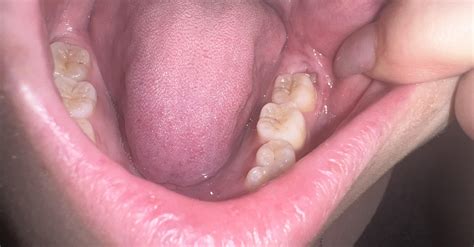

• Swollen Gums: The gum tissue surrounding the area might look red, puffy, or even bleed slightly when you brush.

• Bad Breath or Taste: As the tooth breaks through, a small flap of gum (the operculum) can trap food particles, leading to an unpleasant taste or odor.